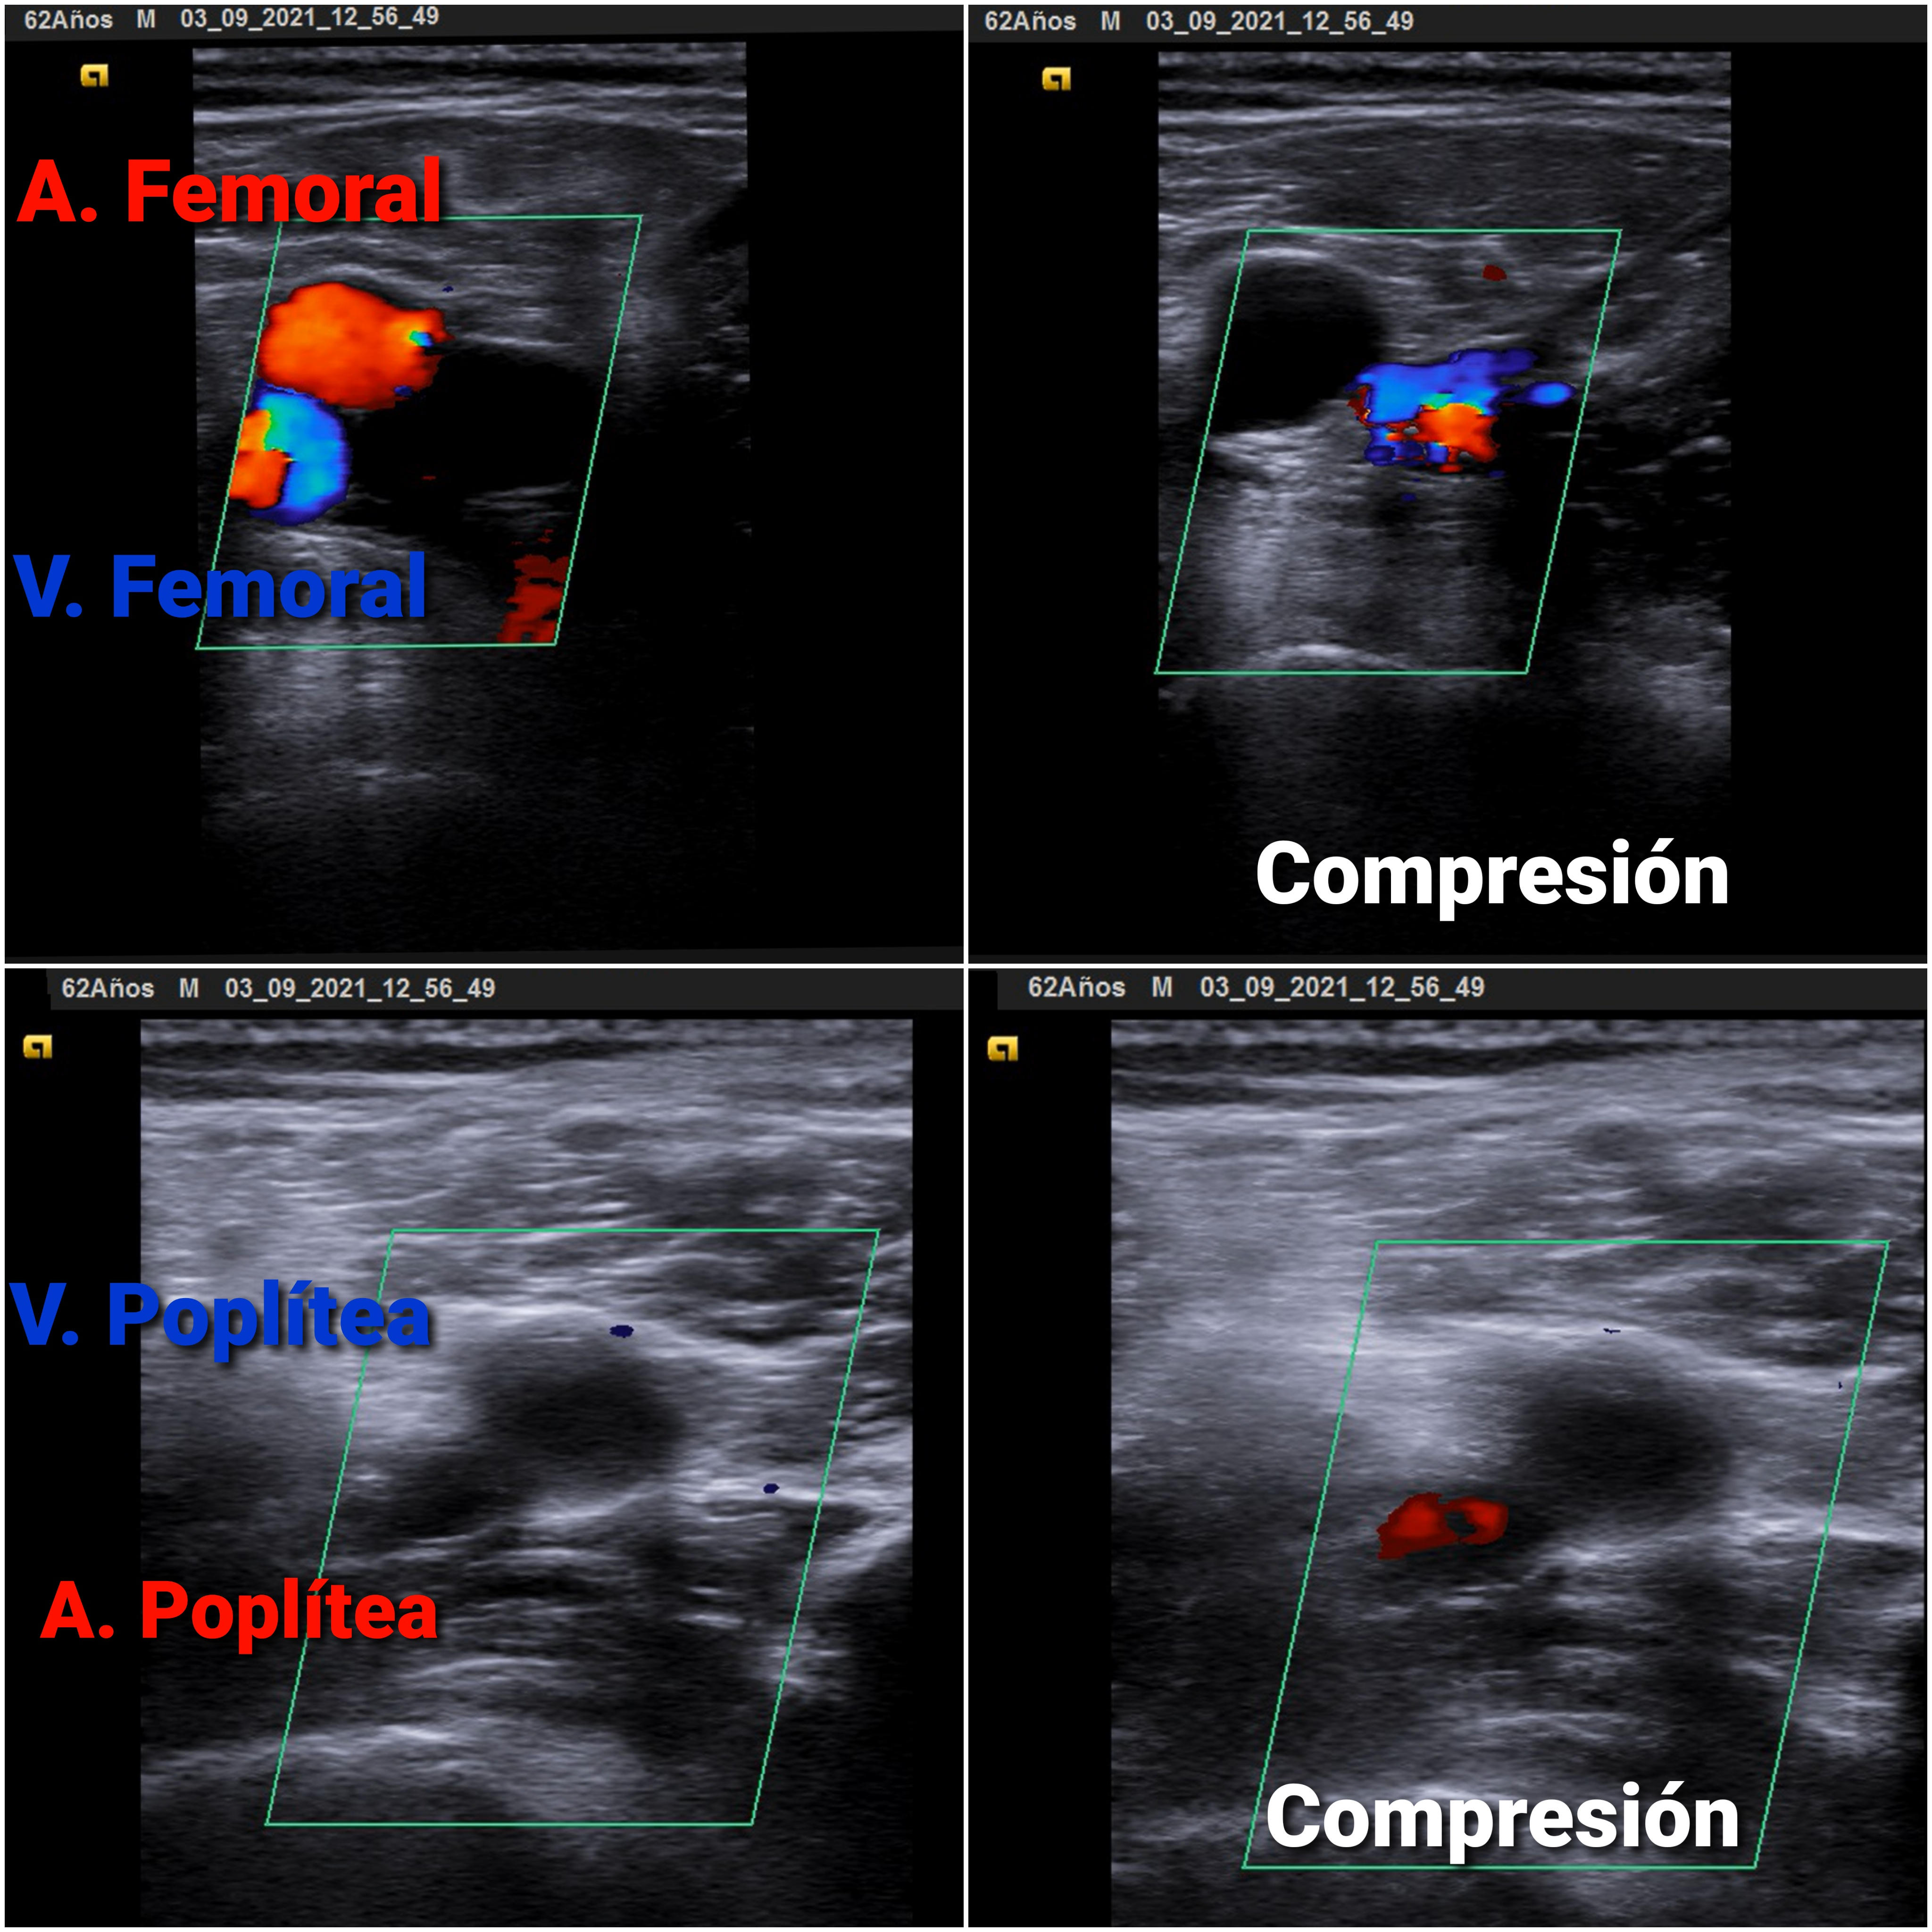

Eco Venosa: no colapso de vena poplítea derecha con signo de la oleada (-).

Trombosis Venosa Profunda (TVP) Poplítea con sospecha de Embolismo Pulmonar (EP)